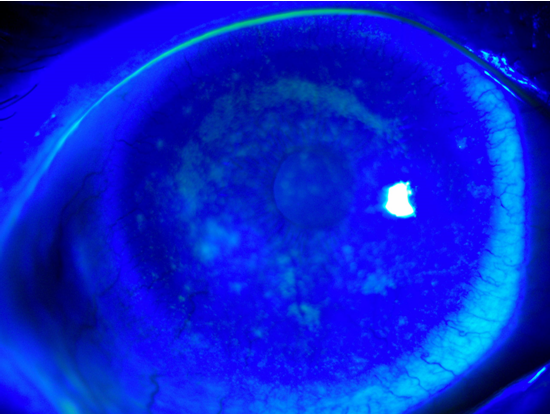

小荆的眼角膜不仅出现了水肿、缺氧的情况,还“爬满”了大量新生血管;

角膜散在大小不等的白色病灶,荧光素染色可见弥漫染色。